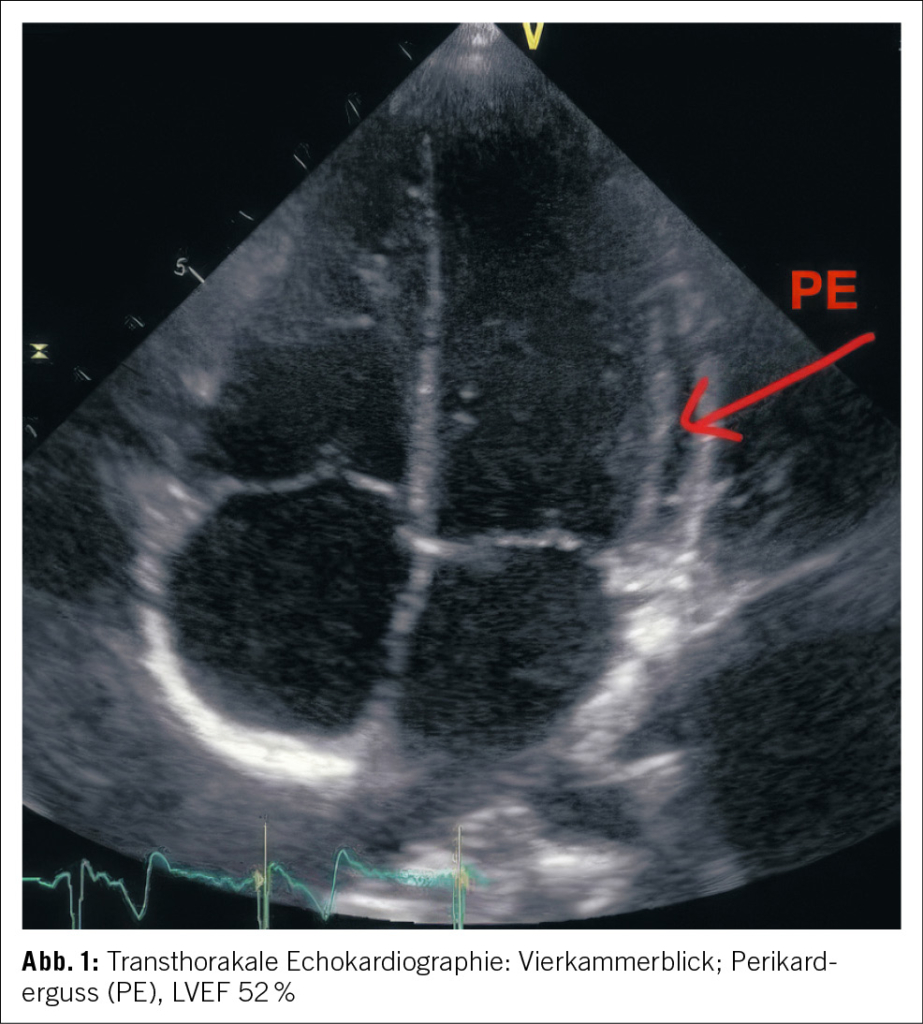

Aufgrund der Gesamtkonstellation wurde rasch die Verdachtsdiagnose eines PIMS-TS mit kardialer, gastrointestinaler, zentralnervöser und hämatologischer Beteiligung gestellt. Zur Diagnosestellung wurden die Kriterien der Schweizerischen Gesellschaft für Intensivmedizin verwendet (4). Im Folgelabor am nächsten Morgen erhärteten die erhöhten Werte von hs Troponin I und NT-proBNP, die charakteristische zunehmende Thrombo- und Lymphopenie und auch eine Hypochloridämie und Hypokalzämie die Verdachtsdiagnose (Tabelle 1). Eine transthorakale Echokardiographie zeigte einen kleinen Perikarderguss (Abbildung 1) und eine leichtgradig verminderte systolische linksventrikuläre Funktion (LVEF 52 %; Globaler Longitudinaler Strain –16 %).

• Leitsymptome sind hohes Fieber, gastrointestinale Beschwerden (Bauchschmerzen, Erbrechen, Diarrhoe), kardiovaskuläre Dysfunktion (Hypotonie, Schock) und neurologische Auffälligkeiten (Kopfschmerzen, Encephalopathie). Diagnostisch wegleitend können erhöhtes Troponin und NT-proBNP sowie echokardiographische Befunde (verminderte linksventrikuläre Auswurffraktion, Perikard- und Pleuraergüsse) sein.